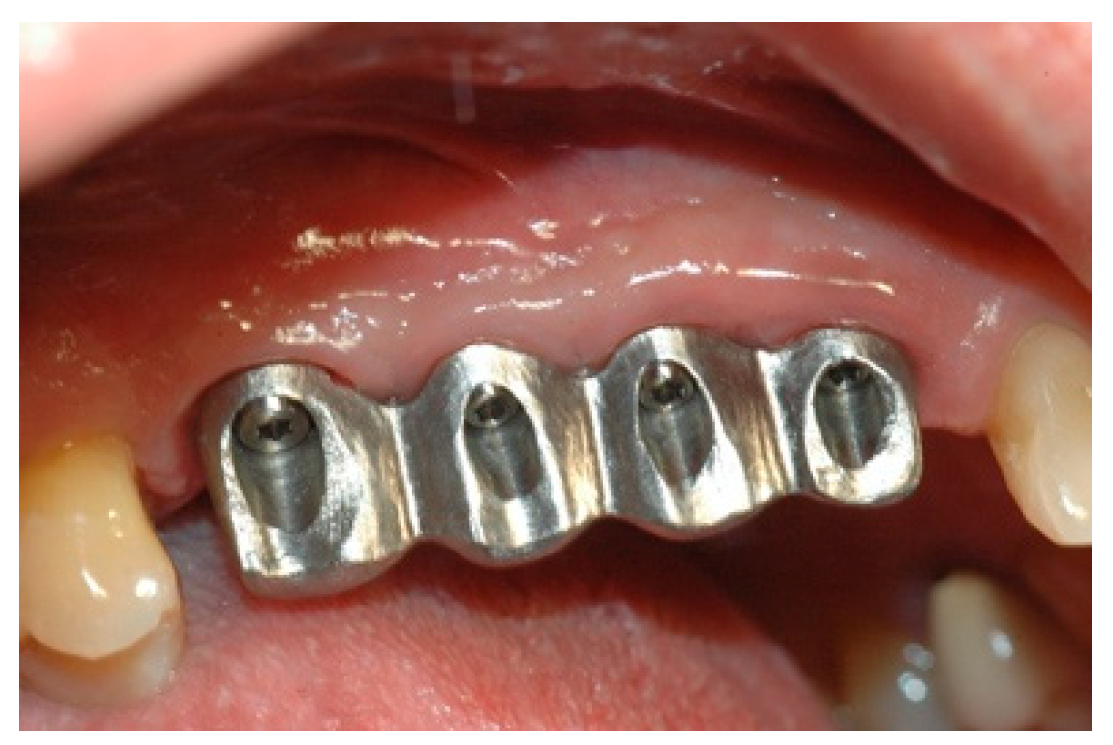

Once the mesostructure was made, it was checked to verify passive adaptation and its precise coupling with the arched fixtures (Figure 8 and Figure 9).

Figure 8. Mesostructure test.

Prosthesis 02 00023 g008

Figure 9. Mesostructure test.